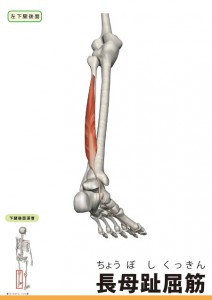

解剖学シリーズ、本日は長母趾屈筋です。

この筋肉は腓骨体の後ろから始まり、アキレス腱の下を通り、母趾の末節骨底に停止します。

筋肉の特徴として腓骨から母趾側に行く為に脛骨後面から着き始まる長趾伸筋腱と足底で交差する為、母趾が屈曲すると第2〜4趾も屈曲します。

作用は母趾屈曲、足部回外、足関節底屈です。

距骨から見た長母趾屈筋は有り難い存在でもあります。

その理由は距骨後方にある長母趾屈筋腱溝を通過する長母趾屈筋は腱が緊張することにより、距骨が後方移動しなよいように、バンパーの役割を担っています。

反対にこの長母趾屈筋が癒着や拘縮により働きが乏しくなると足関節の背屈制限にもなるので大事な筋肉です。